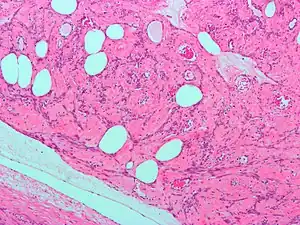

Micrograph of a lipoleiomyoma, a type of leiomyoma. H&E stain.

Microscopically, tumor cells resemble normal cells (elongated, spindle-shaped, with a cigar-shaped nucleus) and form bundles with different directions (whorled). These cells are uniform in size and shape, with scarce mitoses. There are three benign variants: bizarre (atypical); cellular; and mitotically active.